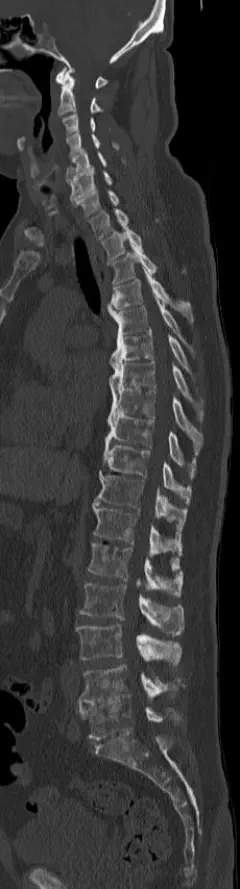

Osteoplastische Knochenmetastasen zeichnen sich dadurch aus, dass Krebszellen den Knochen angreifen und eine übermäßige Bildung von neuem Knochengewebe anregen, was zu einer Verdichtung und Sklerosierung des Knochens führt. Die jedoch die Knochenstabilität nicht verbessert. Die im Gegensatz zu Osteolytische Metastasen bei denen Knochen abgebaut wird. (Zum Beispiel Löcher, dünne Knochen und dünne Knochenränder)